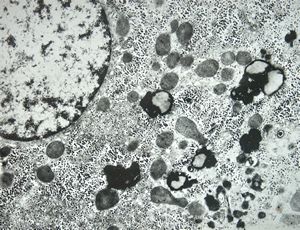

F,3y. | extracellular cholestasis- dilated primary bile duct filled withgranular material

F,3y. | extracellular cholestasis- reduced microvilli in primary bile duct